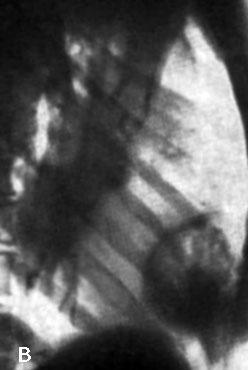

Только сейчас понял, что говорим о разном. Что помечено стрелками, какие мнения?

То, что показываете вы, по-моему имеет отношение к куполу диафрагмы, она какая-то вся релаксированная ( по типу волнообразной релаксации).

Спасибо. Значит "это" релаксация диафрагмы?

А, сейчас осталось разобраться с "биполярным участком", помеченном стрелками?

И, возможно это "остаток" давно минувших дней, который в своё время протекал примерно так..., а возможно, и был не лечен. Можно предположить, что и не обязательно туберкулёз, а "сурьёзная" пневмония...